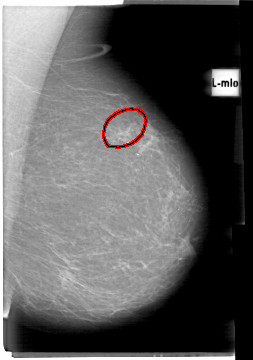

D_4055_1.LEFT_MLO

LEFT_MLO LINES 5386 PIXELS_PER_LINE 3781 BITS_PER_PIXEL 12 RESOLUTION 43.5 OVERLAY

FILE: D_4055_1.LEFT_MLO.OVERLAY

TOTAL_ABNORMALITIES 1

ABNORMALITY 1

LESION_TYPE MASS SHAPE IRREGULAR MARGINS ILL_DEFINED

ASSESSMENT 0

SUBTLETY 3

PATHOLOGY BENIGN

TOTAL_OUTLINES 1

BOUNDARY